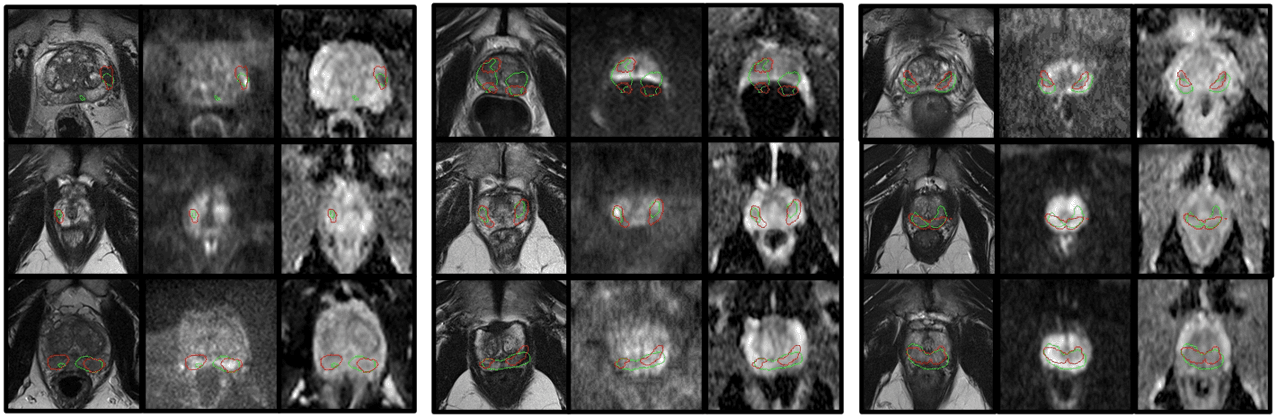

Pilot award

This team is developing AI software that analyses MRI images collected in patients on active surveillance over time to track changes in prostate tumours. The aim is to detect cancer progression early and automatically.

Project leads: Dean Barratt, Geoffrey Sonn

Collaborating institutions: University College London, Canary Center at Stanford (prior partner)